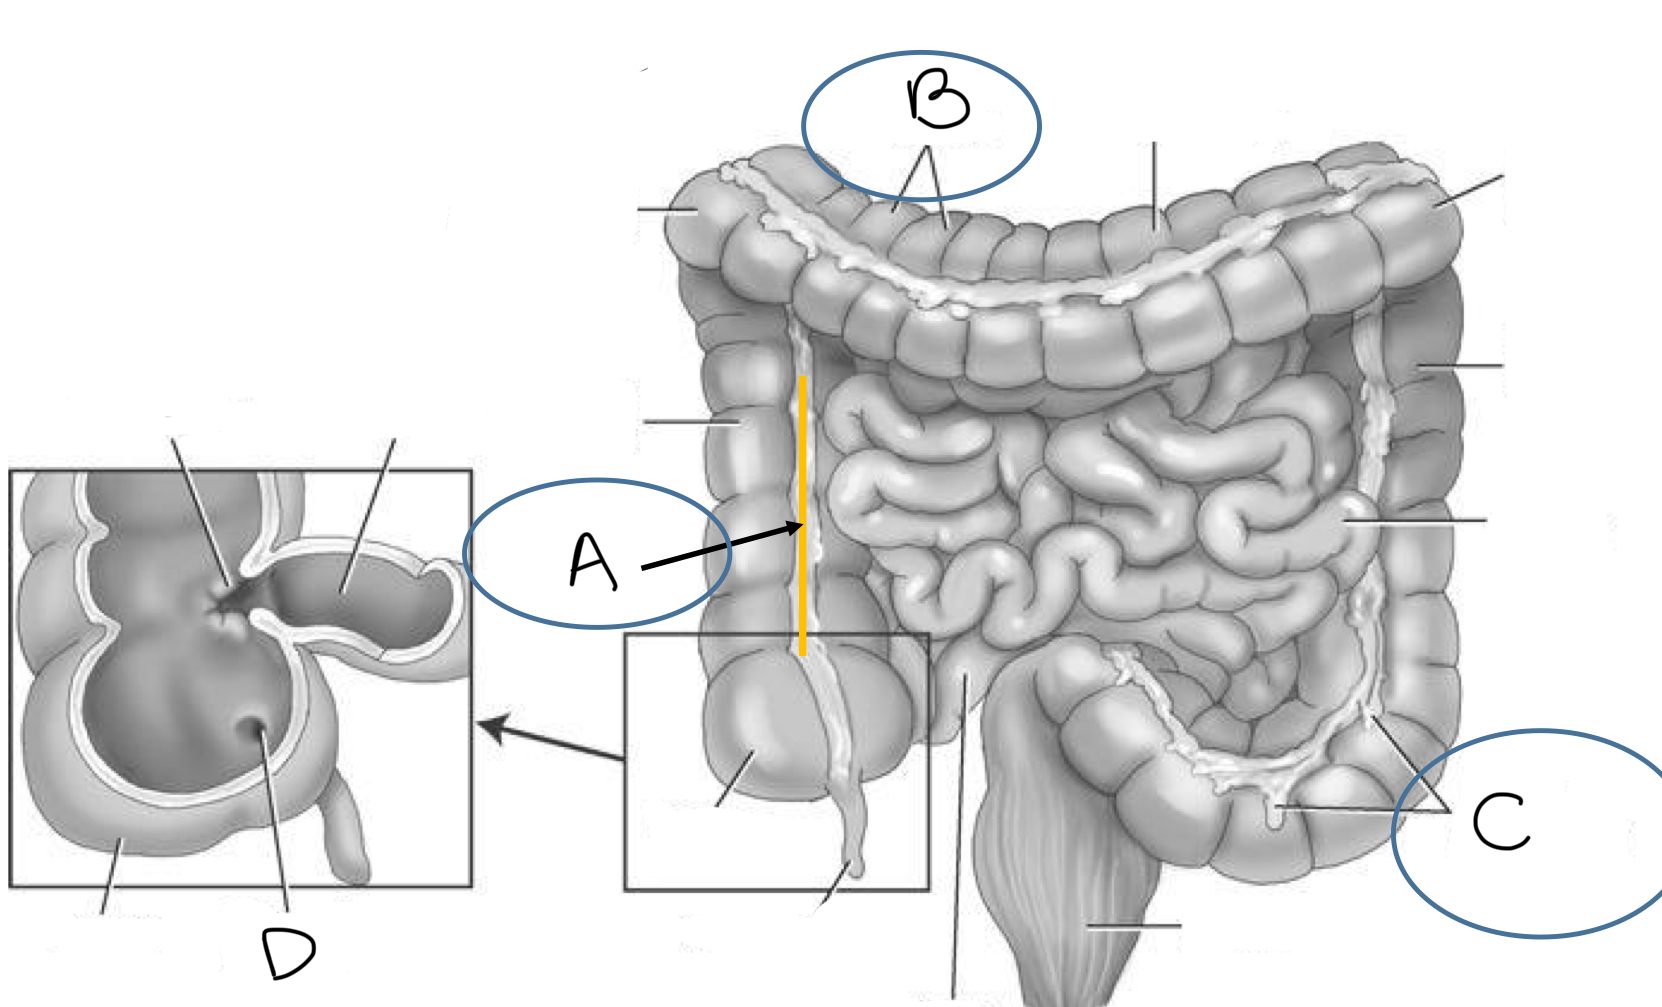

What is A

hepatic (right colic) flexure

What is B

ascending colon

What is C

ileocecal valve

What is D

cecum

What is E

vermiform appendix

What is F

ileum

What is G

mesentery

What is H

rectum

What is I

external anal sphincter muscle

What is J

superior rectal artery and vein

What is K

anus

What is L

sigmoid colon

What is M

sigmoid artery and vein

What is N

descending colon

What is O

inferior mesenteric artery and vein

What is P

splenic (left colic) flexure

What is Q

transverse colon